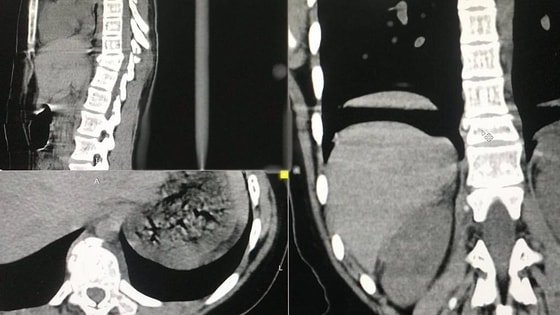

В Ташкенте мужчина избил парня до перелома позвоночника

Несколько дней назад в социальных сетях распространилась информация о том, что в Ташкенте 18-летний парень оказался в больнице с переломом позвоночника после драки с 40-летним мужчиной.